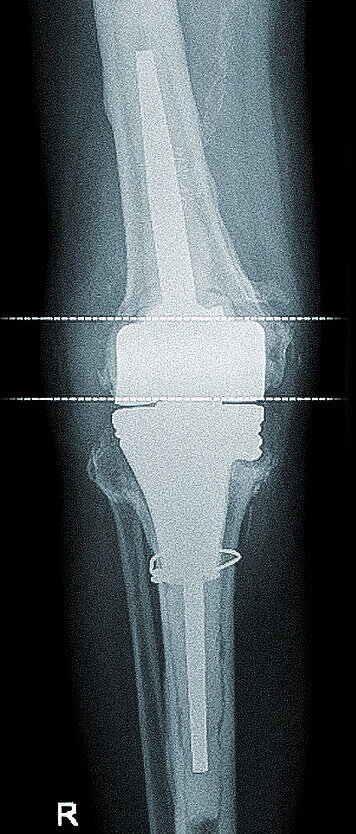

Preoperative X-rays show a revision knee prosthesis with a correct fit and clear signs of loosening in the tibia and the retropatellar replacement (1, 2); planning approach with a standard tibial cone, which proved to be too small in the largest available version (3, 4).

While X-ray diagnostics showed tibial implant loosening and a patella baja, the femoral part of the prosthesis was firmly anchored radiologically and scintigraphically; a knee arthrocentesis again showed no microbial evidence. Clinically, a non-irritant healed scar without any sign of infection was found with a pronounced intraarticular effusion, which was seen in an X-ray image with predominantly dorsal synovial thickening. The extension/flexion was 0–5–95°.